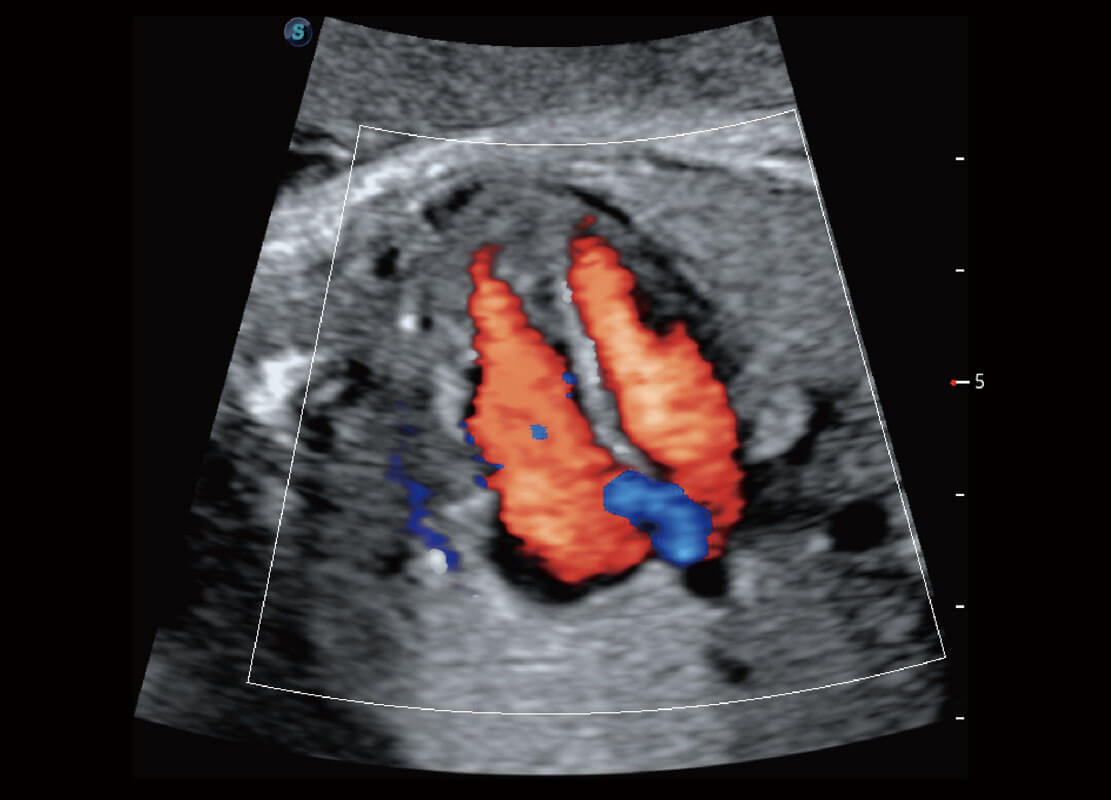

P60搭载一系列胎儿心脏成像技术,实现精细的胎儿心脏评估。

四腔切面

四腔心血流

右室双出口

胎心容积成像